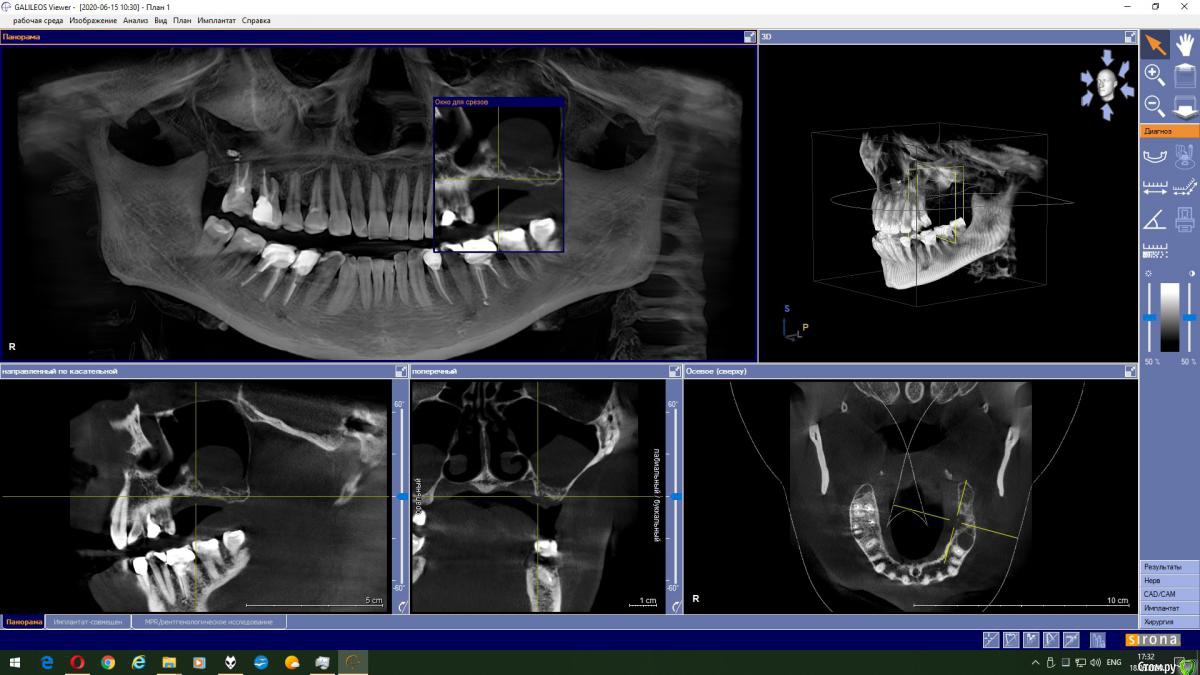

Magnoliya Опубликовано 18 июня, 2020 Поделиться Опубликовано 18 июня, 2020 Здравствуйте, прошу Вашей помощи и консультации. Все доктора, у которых я уже побывала говорят противоположные вещи, сложно принять решение. Очень надеюсь, что вы сможете посмотреть КТ, и выскажете своё мнение. http://fayloobmennik.cloud/7398744 Предыстория удалила 6 и 7 на левой верхней челюсти в надежде, что через 4 месяца сделаю открытый синус-лифтинг с подсадкой костной ткани и затем установлю импланты,но когда принесла КТ врачу перед операцией, он сказал, что синус лифтинг противопоказан, так как в гайморовой пазухе киста, и костной ткани мало, от слова ОЧЕНЬ МАЛО. В его видении решении моей проблемы был скуловой имплант Zigoma. при котором сразу после операции я выйду с зубами, естественно с другой суммой на операцию, на которую я не расчитывала. Тут я решила пойти на консультацию к другим специалистам, чтоб принять решение. На сегодняшний день есть 3 варианта, которые озвучили мне доктора: 1. Операция со скуловым имплантом с одномоментной установкой коронок2. Обратиться к ЛОРу и удалить кисту, затем синус лифтинг и т.д.3. Один врач сказал мне, что киста не мешает и можно делать синус лифтинг не удаляя кисту??? Действительно ли так? Можно ли избежать операции по удалению кисты? Заранее спасибо всем тем, кто хоть как то поможет советом Ссылка на комментарий

колесников Опубликовано 18 июня, 2020 Поделиться Опубликовано 18 июня, 2020 Глупости какие! Для чего зигомы? Доктора видимо смутил рельеф дна пазухи,там много перегородок,выступов,что затрудняет отслаивание мембраны. Можно провести имплантацию одновременно с синуслмфтингом,а кисту и вовсе не трогать. 1 Ссылка на комментарий

Irouil Опубликовано 18 июня, 2020 Поделиться Опубликовано 18 июня, 2020 Надо смотреть контур, конечно, но если позиция зигомы транссинусальная (судя по всему это так), то отношения с кистой не лучше, чем при синус лифте) Ссылка на комментарий

Bier Опубликовано 18 июня, 2020 Поделиться Опубликовано 18 июня, 2020 Данную кисту убирать не нужно. Нет показаний для зигомы. Делайте синуслифтинг и имплантат. Ссылка на комментарий

колесников Опубликовано 19 июня, 2020 Поделиться Опубликовано 19 июня, 2020 Выходить можно сделать синус лифтинг не трогая кисту. В дальнейшем ничем это не грозит? Я имею ввиду киста не вытечет на импланты? И может ли киста со временем рассосаться сама? это не инфекционного происхождения киста,слизистая железка закупорилась,может надуваться,может лопнуть самостоятельно,у вас она на боковой стенке пазухи,синуслмфтингу не помеха Ссылка на комментарий